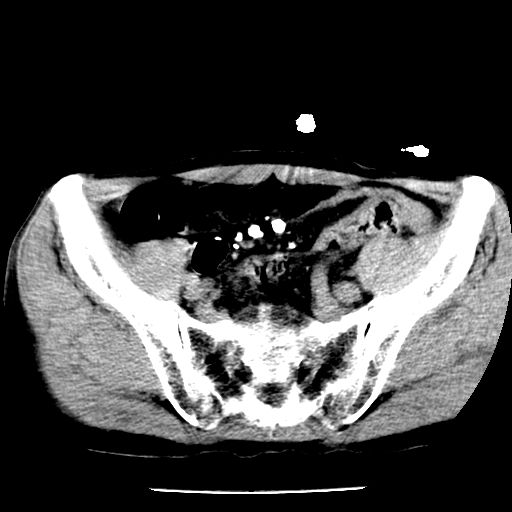

男,59岁,“结核性胸膜炎”30余年,胸部经常疼痛,多次x检查提示“肺部”炎症。腹部疼痛5日,b超提示:“肝内短管结石,余显示不清,建议进一步检查。”

两肺结核并右侧胸腔积液;脾脏、腹腔及腹膜后淋巴结结核[陈旧性];肝内胆管结石

胸部腹部都是结核(双肺。纵隔淋巴结,肝脏,脾脏,肠系膜)

两肺结核并右侧胸腔积液;脾脏、腹腔及腹膜后淋巴结结核[陈旧性];肝内胆管结石。直肠息肉?